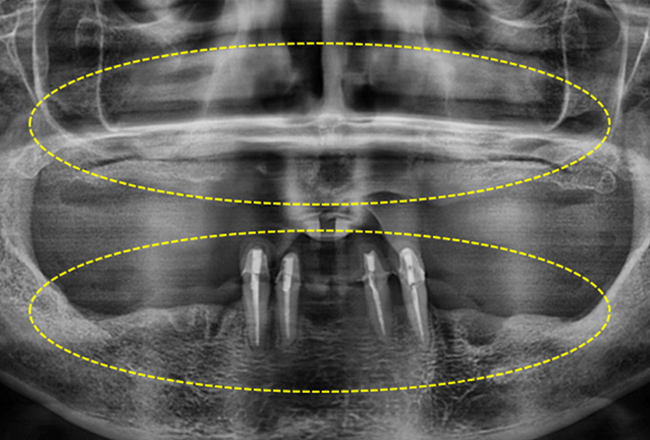

구강 상태와 잇몸 뼈를 정밀하게 진단한 후

개인에게 맞는 계획으로 임플란트를 식립합니다.

전체 임플란트 환자 중 고령자가 대부분이기 때문에

환자의 건강상태와 당뇨 등 임플란트 시술 시 영향을 주는

질환 유무를 잘 파악하고 그에 맞는 적절한 치료를 진행해야합니다.